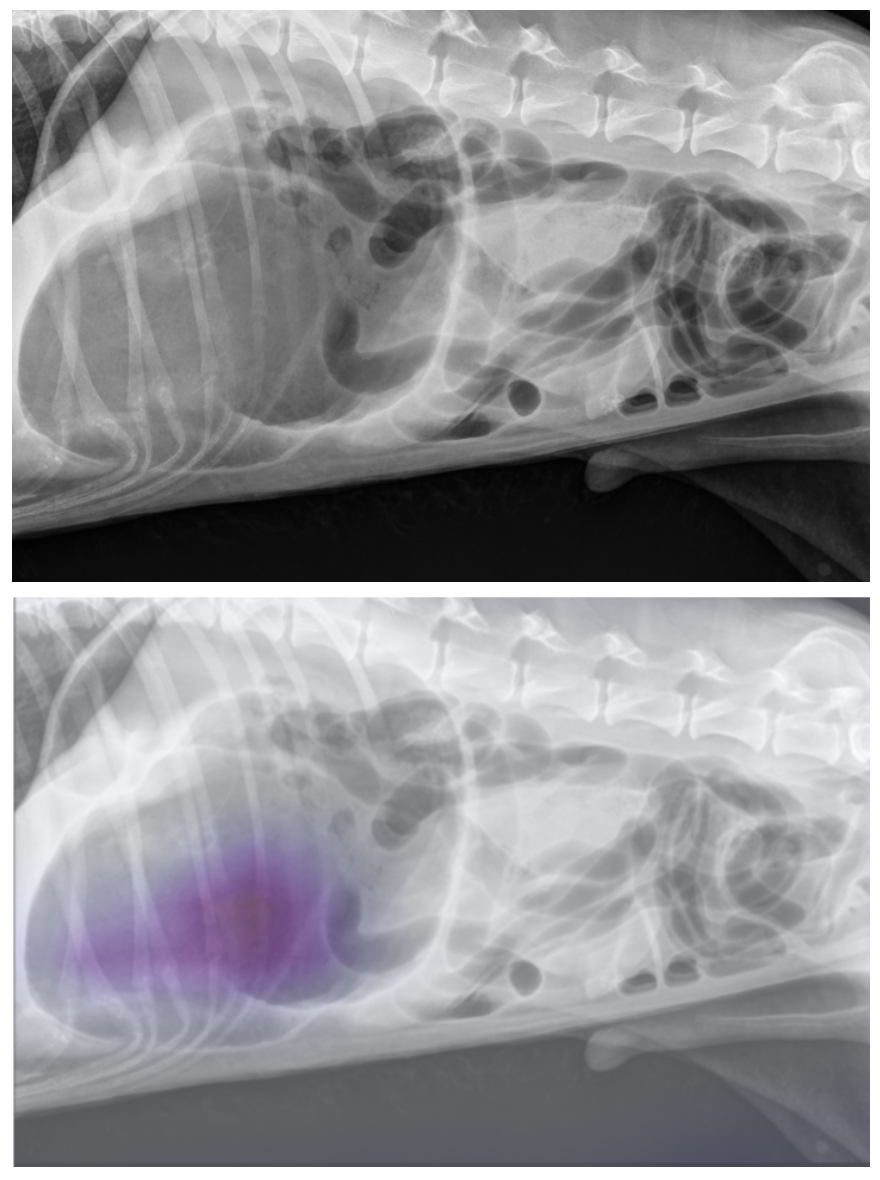

Instant AI Insights for Critical Conditions

Radimal’s AI automatically scans every canine and feline x-ray and delivers near-instant assessments. With critical conditions like obstruction, heart failure, and GDV flagged immediately, your team can prioritize urgent cases and improve patient outcomes—without extra clicks.